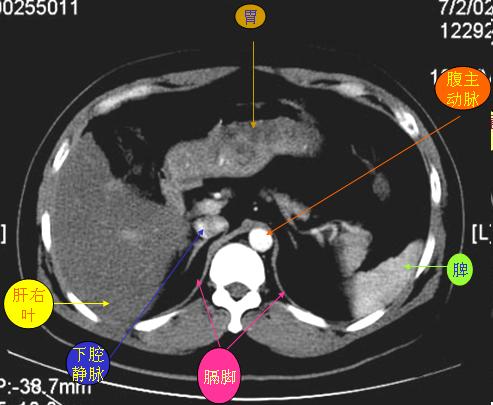

腹部ct解剖与基本病变